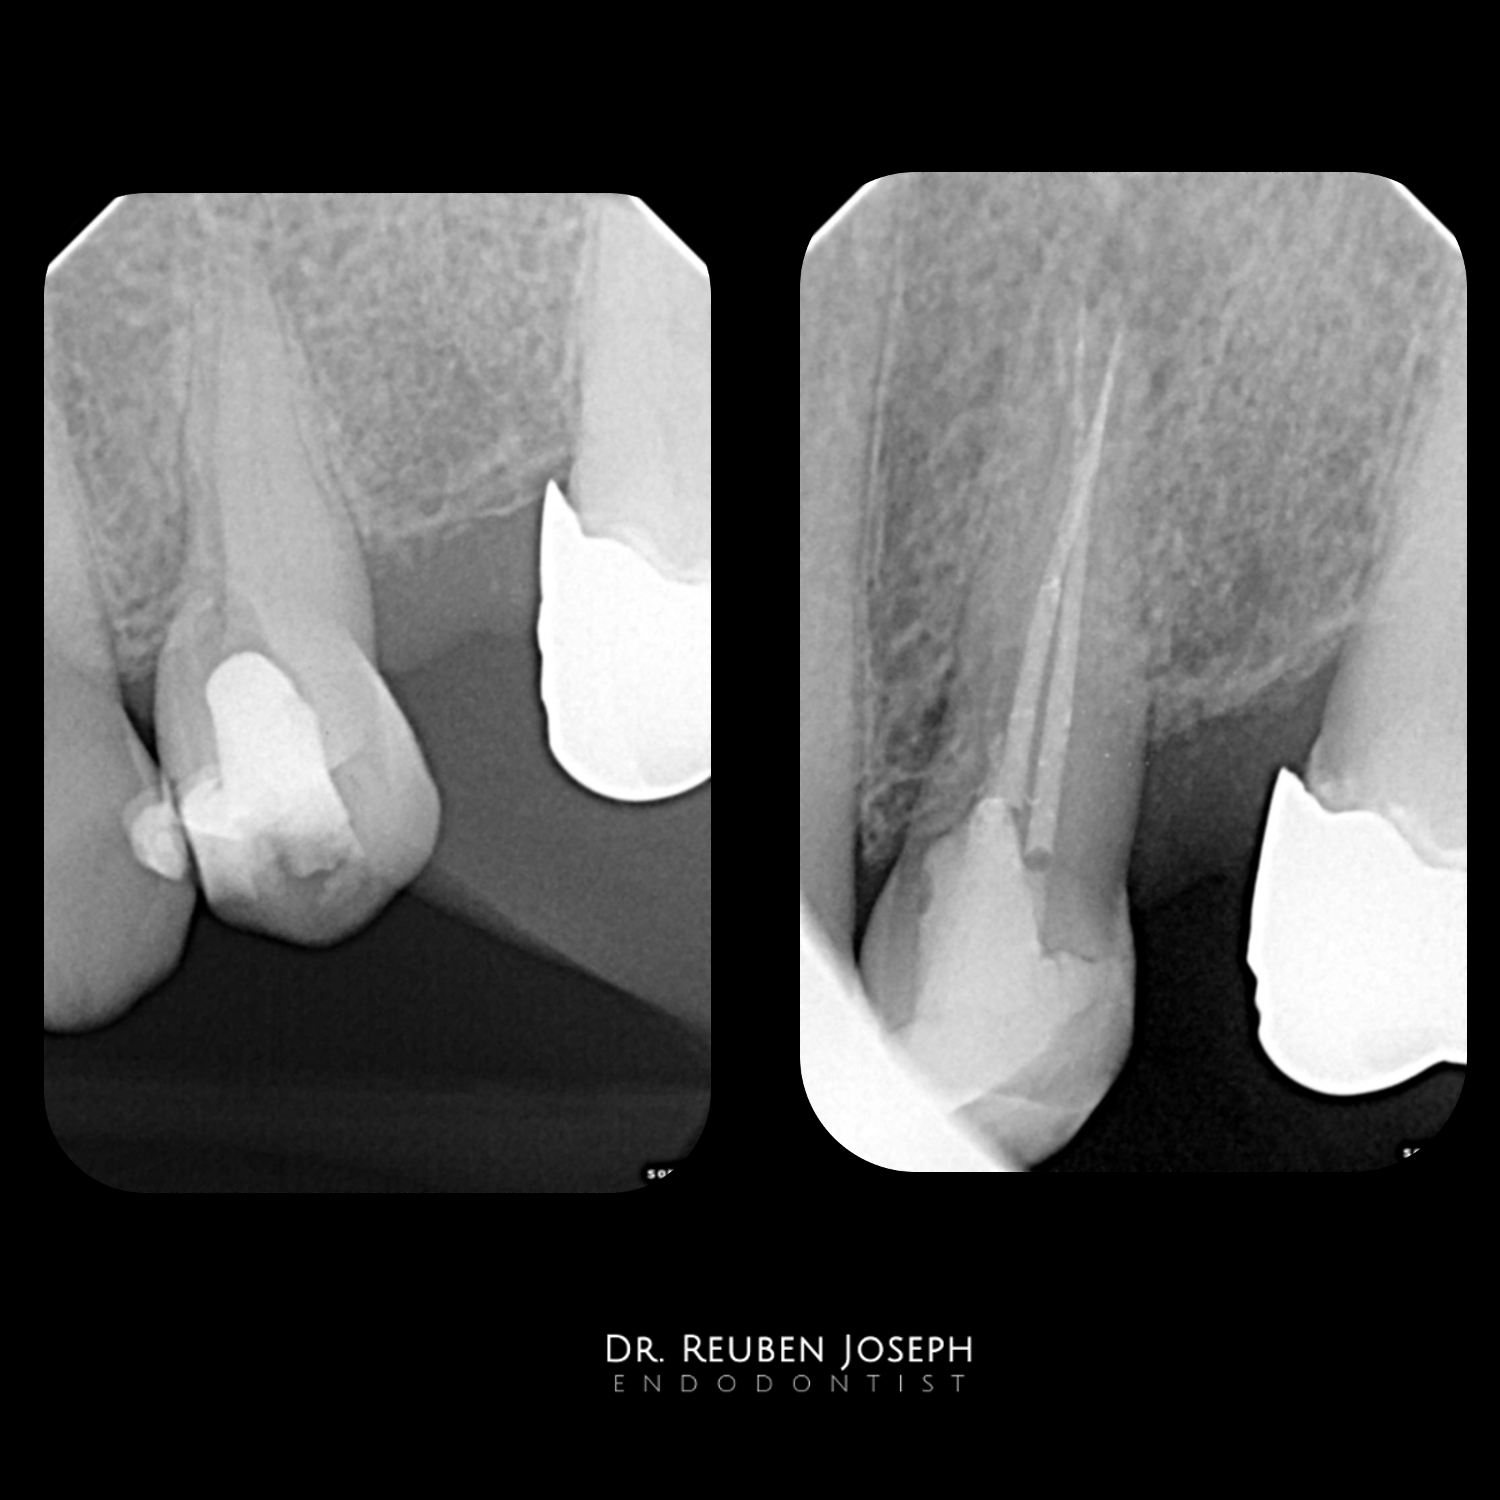

#24 with a Iatrogenic perfortion/ Calcified canals/ fracture in the distal wall

Pre-op Clinical

# in the distal wall

Perforation

Palatal canal located

Buccal canal located

Perforation site prepared

Slim preparation to prevent further dentin loss